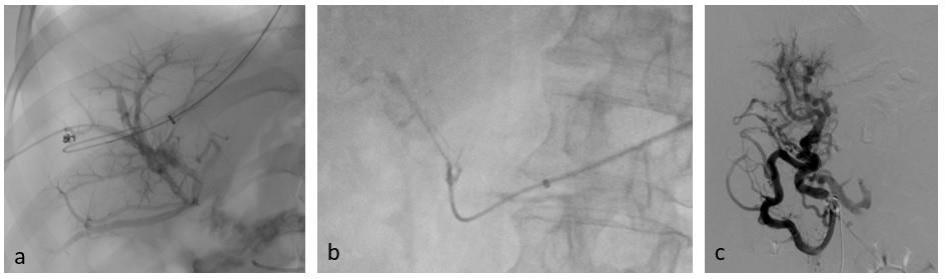

内脏系统可通过经颈静脉或其他经皮穿刺途径(包括经肝、经脾或经肠系膜路径)进行介入治疗,其中经肠系膜路径也可通过小切口开腹手术完成(图3)。

图3. 内脏系统的入路途径(图源自文献)

这些方法联合应用可提高手术成功率。导管超选至闭塞段后,首先进行血管成形术。若未充分开通,则可置入支架以维持静脉血流。若采用经肝或经脾途径,必须对穿刺道进行栓塞,以避免出血并发症。